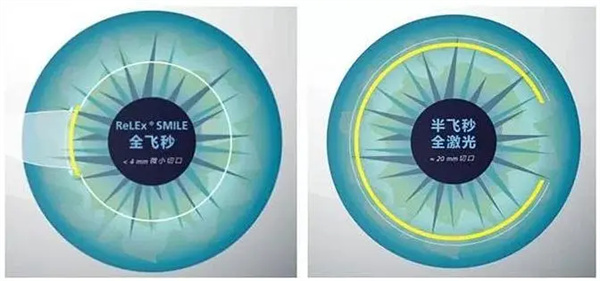

小儿斜弱视与屈光专科:早矫干预医生

谭可主治医师在青少年近视防控方面颇有建树,创新"角膜塑形镜+视觉训练"联合方案,年控制近视进展50度的达标率达76%。邵杰医师同时在小儿斜弱视治疗领域造诣深厚,其设计的"家庭视觉游戏包"能有效缩短双眼视功能重建周期至3个月。